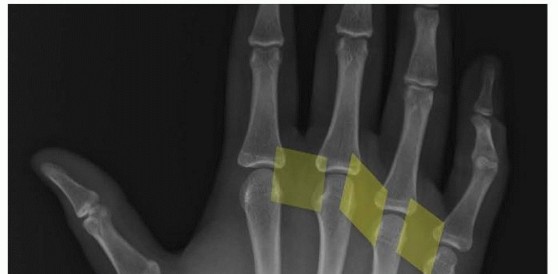

29 MIN READ Reconstruction of Chronic Radial and Ulnar Instability of the Thumb Metacarpophalangeal Joint يناير 2023 Read More